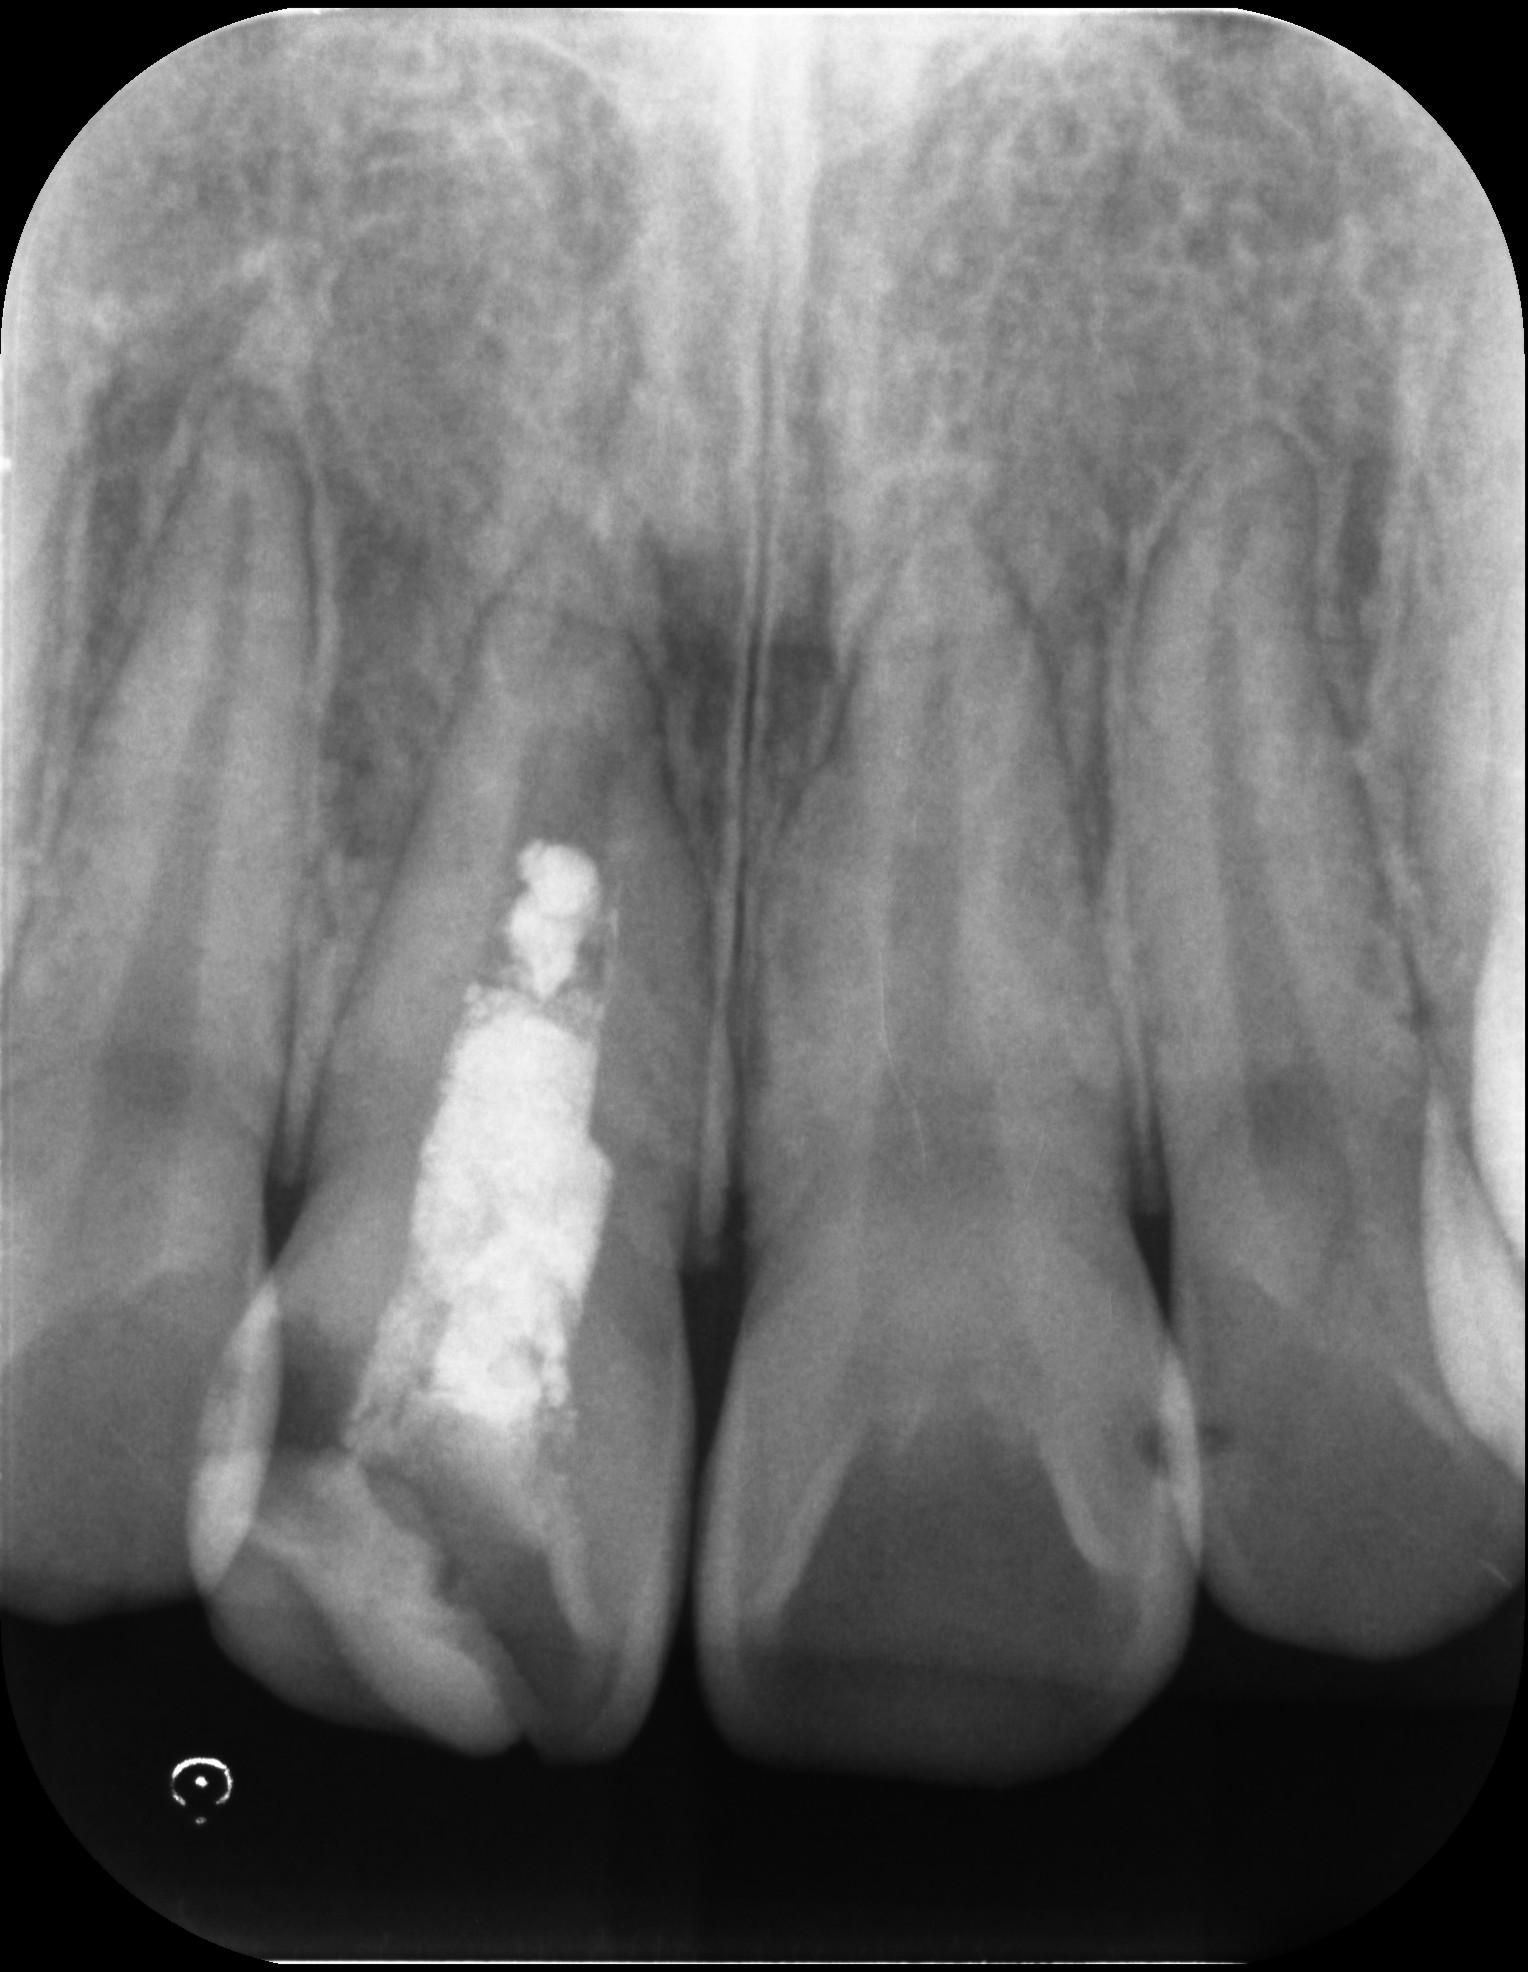

根管治療で前歯を残した症例

タップで写真の拡大ができます。

Before

After

主訴

歯茎が腫れている。変色も気になる。

治療内容

イニシャルトリートメント(初回根管治療・前歯)

ウォーキングブリーチ、レジンコア

治療期間

1ヶ月

治療費用

143,000

治療の

リスク

根尖部透過像が完全に消失しない可能性があります。

色が後戻りする可能性があります。